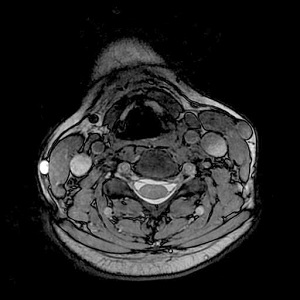

COSMIC employs a fully-balanced, oscillatory-state, coherent-imaging pulse sequence with segmented multi-shot centric k-space acquisition technique. The center of k-space that contributes to image contrast is filled during the oscillatory state.

COSMIC images have improved disc, muscle, bony structure and grey/white matter contrast, and higher SNR in comparison to 3D FIESTA images given similar scan parameters for a C-spine scan. It also reduces distortion due to susceptibility or chemical shift in comparison to GRE and FIESTA pulse sequences.

Use these steps to acquire 3D axial C-spine images. The k-space filling technique used with COSMIC improves the CNR and SNR of C-spine tissue, including the spinal cord, vertebral disks, nerve root canal, and contrast between CSF and nerve roots. 3D COSMIC images improve depiction of osteophytes and foraminal nerve roots. It produces a mixed T2, T2/T1 image contrast.